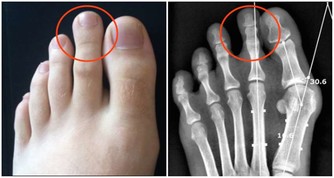

4、若因骨刺引起關節疼痛,可以用手術方法切除骨刺,也可採用微創療法。